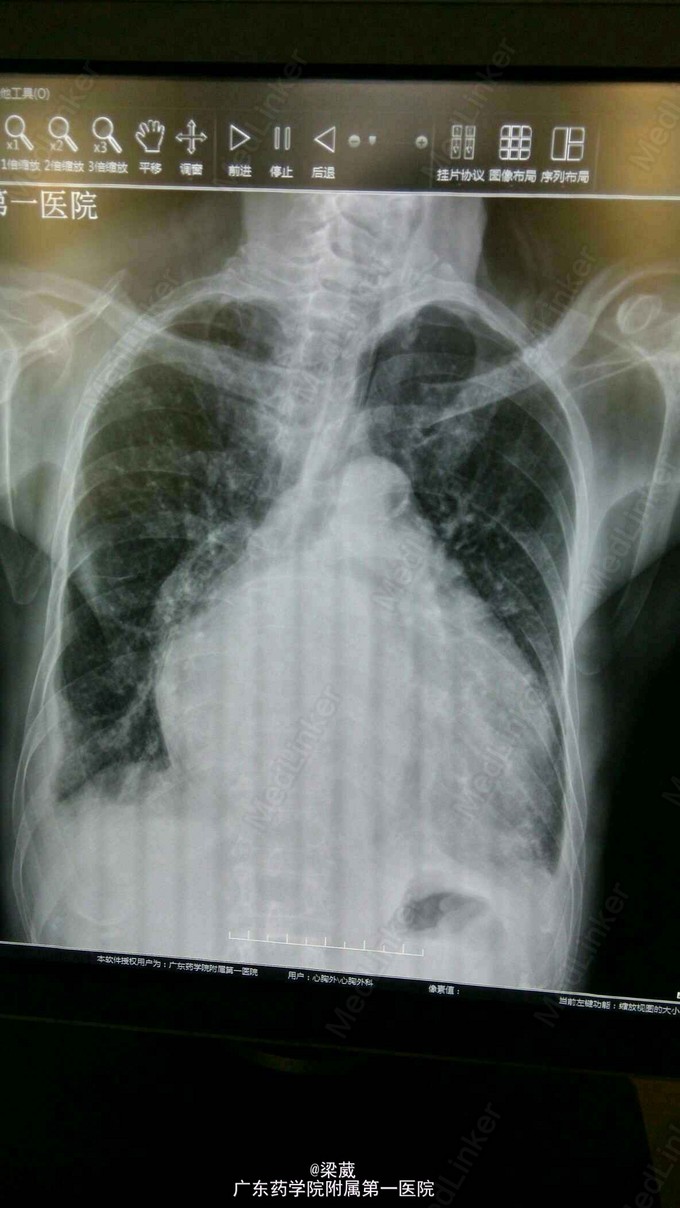

血压:131/65mmHg。神清,呼吸稍促,口唇稍苍白。双侧鼻唇沟对称,伸舌居中。双颈静脉怒张,肝颈征阴性。桶状胸,双肺呼吸音清,双肺底可闻及明显湿罗音。心前区抬举样搏动,剑突下搏动明显,心界左扩,心率121次/分,房颤律,心尖区可闻及5/6级收缩期吹风样杂音及3/6级舒张期隆隆样杂音,向左腋下传导,主动脉瓣第一听诊区可闻及3/6级收缩期喷射样杂音及2/6级舒张期哈气样杂音,三尖瓣听诊区可闻及3/6级收缩期吹风样杂音,向心底部传导,肺动脉瓣听诊区可闻及2/6级收缩期吹风样杂音,P2亢进,未闻S3、S4。腹平软,剑突下及左上腹部可有轻压痛,无反跳痛,余腹无压痛、反跳痛。未触及腹部包块,肝脏肋下2横指可及,脾脏肋下未触及,Murphy 征可疑阳性。双下肢中度浮肿。 辅助检查:肾功(三项):尿素氮 12.990(mmol/L),肌酐 126.000(umol/L);脑钠肽测定:640.700(pg/ml);胸片+颈椎片 1、风湿性心脏病联合瓣膜病变表现。心功能不全合并肺部感染。建议治疗后复查。2、慢性支气管炎、肺气肿改变。右上肺继发性肺结核(纤维化病灶为主)。3、双侧少量胸腔积液。心彩超:心脏超声, 1、二尖瓣狭窄,瓣口面积0.7cm2,伴轻中度二尖瓣反流。2、左房内附壁血栓形成。3、双房右室内径增大,左室舒张末压增高。4、肺动脉高压,肺动脉增宽,伴重度三尖瓣反流。5、少量心包积液。 2015.8.4行CAG检查,结果提示“呈左冠优势型,LAD闭塞,LCX、RCA未见明显狭窄”。